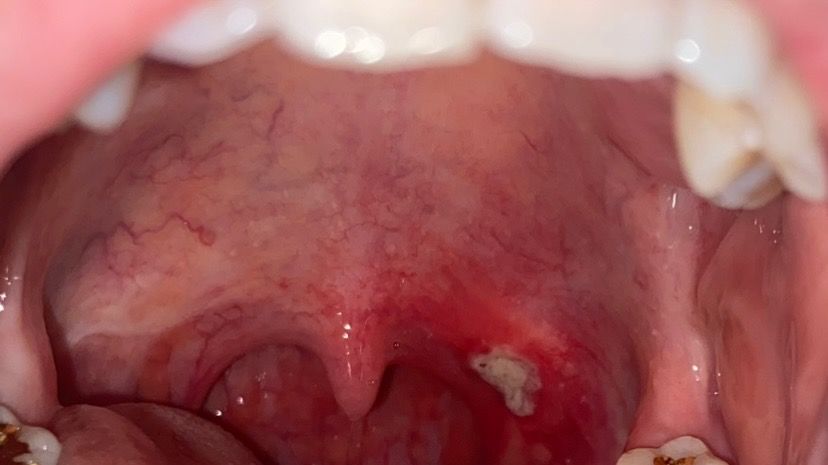

목젖 옆 구내염이 너무 크고 고통스러운데 구강암인가요

생긴지 5-6일쯤 되었고 점점 커지는듯하다가 어제부터는 크기를 유지하고있는데, 혀나 볼에 생겼던 구내염의 고통과는 너무 다릅니다. 생긴 위치때문인지 침이 계속 닿아서 그런지 더 쓰라리고 붓고 열감이 있습니다... 말을 할 때도 아픕니다.

진통제를 먹으면 훨씬 낫긴 합니다만 이렇게 큰 구내염을 처음 겪어서 걱정됩니다.

구강암으로 의심될 모양이나 소지가있는지 궁금합니다.

사진 순서대로, 마지막 제일 큰 모양이 가장 최근 사진입니다.